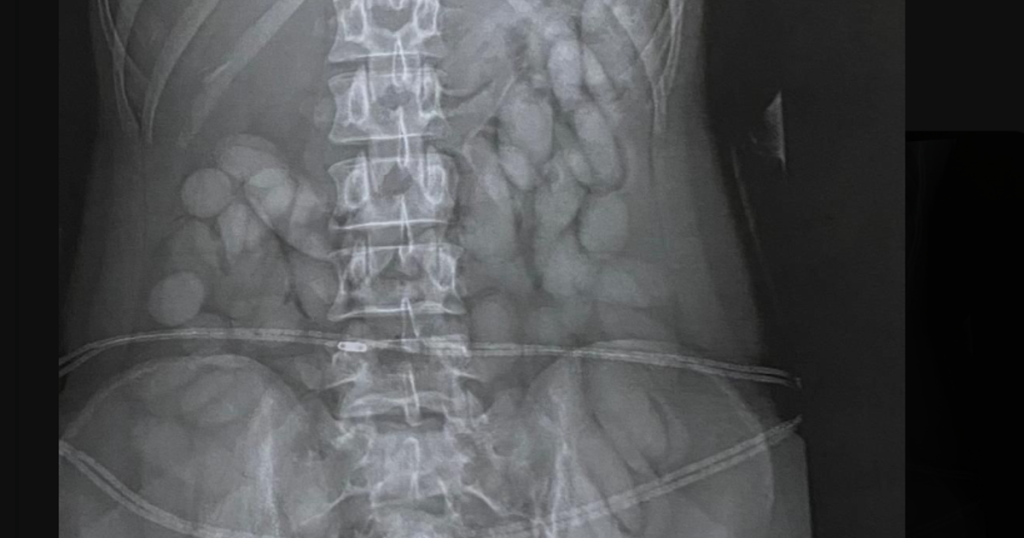

Une radiographie réalisée dans un hôpital voisin a révélé qu’elle avait avalé de petits paquets soupçonnés de contenir de la cocaïne.